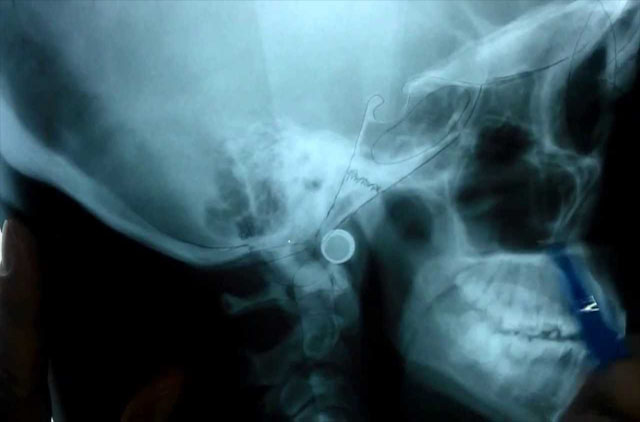

-Lateral de Craneo (LC) 8 x 10¨

-Lateral de Craneo (LC)

-Panoramica (OP)

-Lateral de Cráneo 8x10" (LC)

-Lateral de Cráneo 10x12" (LC)